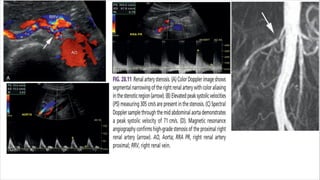

Doppler evaluation of the renal artery stenosis

• Color flow imaging is used to identify blood flow abnormalities that may be stenosis-related, but

spectral Doppler measurements provide quantitative data that are essential for determining the

severity of stenosis.

1. Elevated blood flow velocity within a stenotic segment of the vessel. A Flow velocity is

increased proportional to the degree of luminal narrowing; therefore spectral doppler

measurements can be used to approximate the severity of a stenosis.

2. Doppler-to-vessel angle of 60 degrees or less is mandatory to ensure that velocity information is

accurate.

3. A significant stenosis is accompanied by poststenotic flow disturbance (turbulence).

• The presence of color bruit artifacts, on the other hand, usually indicates a significant flow

abnormality.

• Identification of ragged or “picket fence” waveforms with spectral broadening and bidirectional

flow just distal to the stenotic area is also indicative of significant stenosis